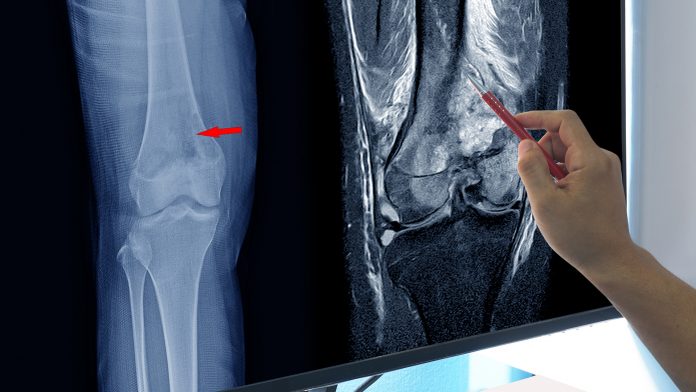

The condition of primary children’s health-care impacts not only the quality of life of the youngest members of our society but also its overall size. Osteosarcoma is one of the most common malignant bone tumours in children and young adults, with more than 900 cases diagnosed each year in the US.

To address this threat, the Nano4Tarmed project aims to develop a new strategy for the treatment of osteosarcoma using a new generation of 2D theranostic nanoplatforms. Current chemotherapy-based treatment usually includes doxorubicin, cisplatin, methotrexate, ifosfamide, and etoposide.4 Notably, the introduction of multimodal treatment improved the overall survival of 65% of treated patients over five years.5 Yet, relapsing or metastatic stages still present fatal outcomes, and side effects of traditional chemotherapy often severely affect the quality of a patient’s life and even shorten the overall survival.